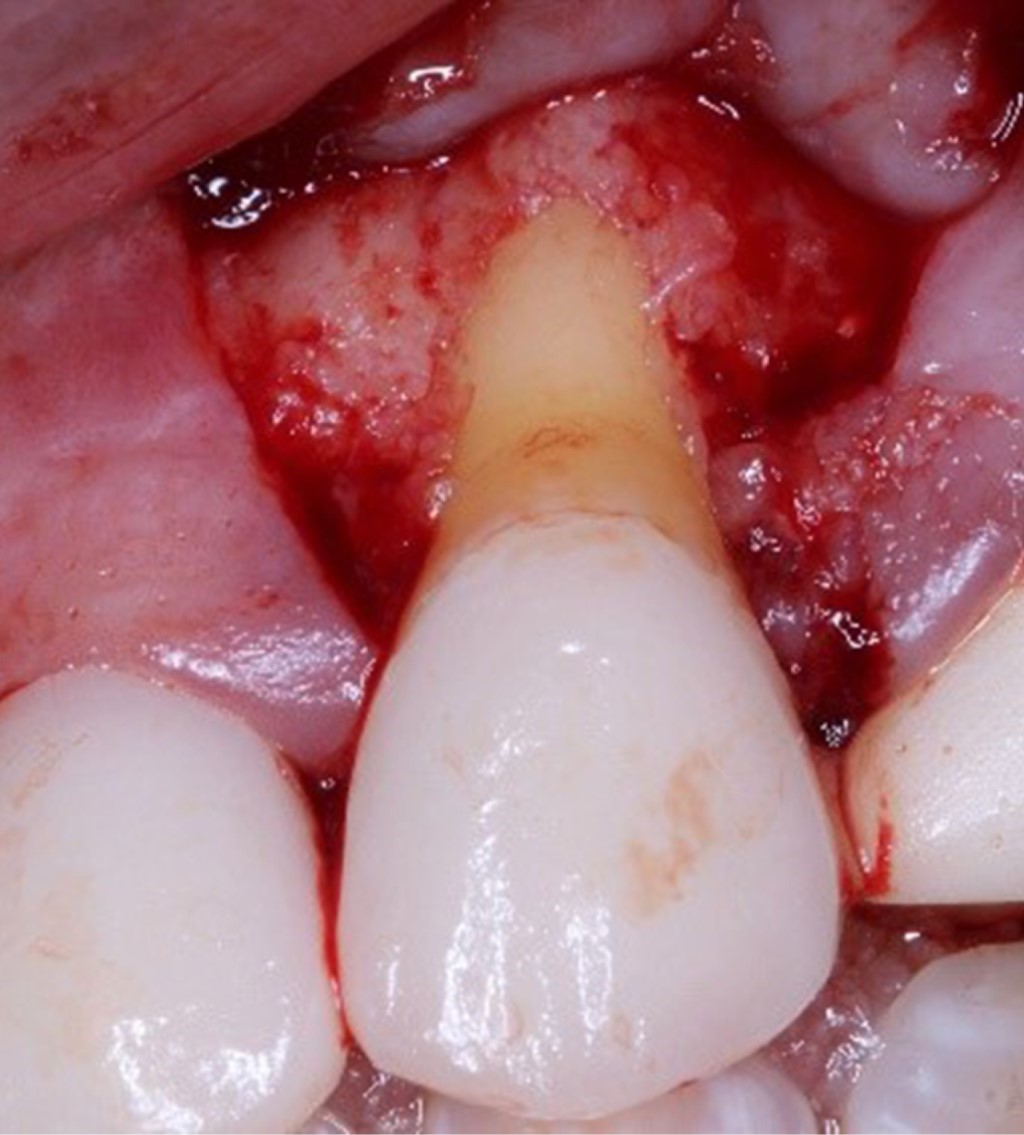

Se realizó la preparación del sitio receptor mediante incisiones oblicuas con bisturí Bard Parker® #3 y hoja de bisturí #15c a nivel de la unión cemento-esmalte en la base de cada papila adyacente, seguido de dos liberatrices oblicuas y una incisión intrasulcular, la cual unía las dos liberatrices. Posteriormente, se realizó la elevación del colgajo de espesor parcial a nivel lateral de las recesiones, elevación de colgajo a espesor total apical a la recesión gingival, continuado hasta la unión mucogingival, donde se realizó una incisión horizontal sobre el periostio para lograr la desinserción y liberación mucosa del colgajo (Figura 3).

Figura 3